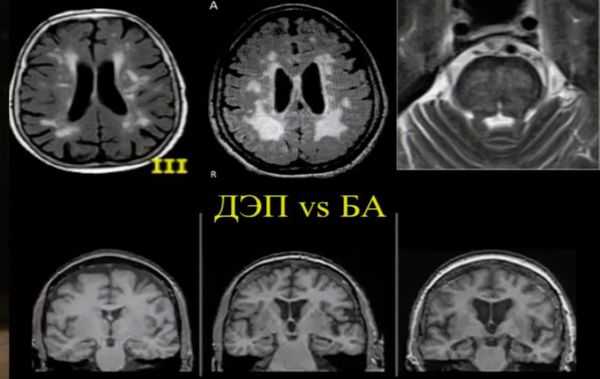

Для выявления и оценки тяжести заболеваний, спровоцировавших развитие сосудистой деменции, больных направляют на консультацию к неврологу, кардиологу, психиатру и другим специалистам. Осуществляют мониторинг артериального давления. Пациентам с сосудистой деменцией назначают МРТ головного мозга, КТ головного мозга, УЗДГ сосудов головного мозга, РЭГ, ЭЭГ и другие исследования. Дифференциальную диагностику проводят с деменцией при болезни Альцгеймера. В пользу сосудистой деменции свидетельствует наличие неврологических нарушений и нерезко выраженные нарушения памяти. При постановке диагноза учитывают возможность развития смешанной деменции, обусловленной как сосудистой патологией, так и болезнью Альцгеймера.

МРТ и КТ проводят для выявления поддающихся лечению причин деменции и нарушений, которые могут усугубить симптомы. Структурные изменения по данным магнитно-резонансной томографии являются более прогностически значимыми для дальнейших изменений в когнитивной сфере, чем биомаркеры цереброспинальной жидкости. По данным магнитно-резонансной томографии, признаки цереброваскулярного заболевания, такие как лейкоареоз и множественные подкорковые лакунарные инфаркты, чаще наблюдаются у пациентов с болезнью Альцгеймера, чем в контрольной группе. [7] Асимметричная атрофия медиальных отделов височной доли также не исключает сосудистую деменцию.

Описана смешанная модель патогенеза болезни Альцгеймера, которая предполагает взаимодействие церебральной амилоидной ангиопатии с сосудистыми факторами на ранних стадиях патологического процесса. Предполагается, что синергия между накоплением амилоида и цереброваскулярной патологией может инициировать дальнейшую дисфункцию нейронов и нейродегенерацию. [8] В этом отношении церебральные микрокровоизлияния, выявляемые в режиме Т2 градиентного эхо на магнитно-резонансной томографии, являются дополнительным и доступным диагностическим маркером, повышающим диагностическую значимость лейкоареоза и свидетельствующим в пользу церебральной амилоидной ангиопатии или гипертонической микроангиопатиии, особенно в случаях смешанной патологии и тяжелого когнитивного дефицита.

Локализация церебральных микрокровоизлияний является дифференциально-диагностическим признаком ведущего патологического процесса. В случае болезни Альцгеймера наблюдается корковая локализация микрокровоизлияний, в случае дисциркуляторной энцефалопатии или сосудистой деменции будут визуализироваться микрокровоизлияния в глубинных отделах мозга. [9] [10]